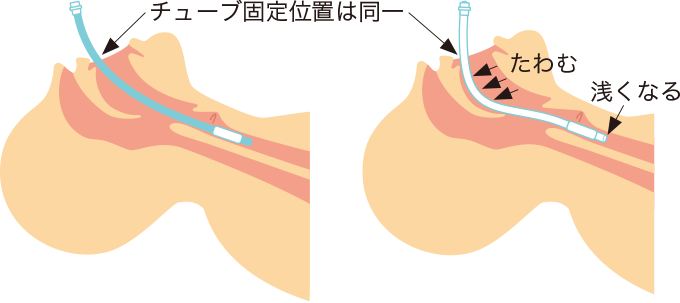

気管チューブの口角の固定テープの位置(女性20~22cm、男性22~24cm)がずれていない場合でも、口腔で気管チューブがたわんでいる場合(図2)があります。

図2気管チューブのたわみと脱出